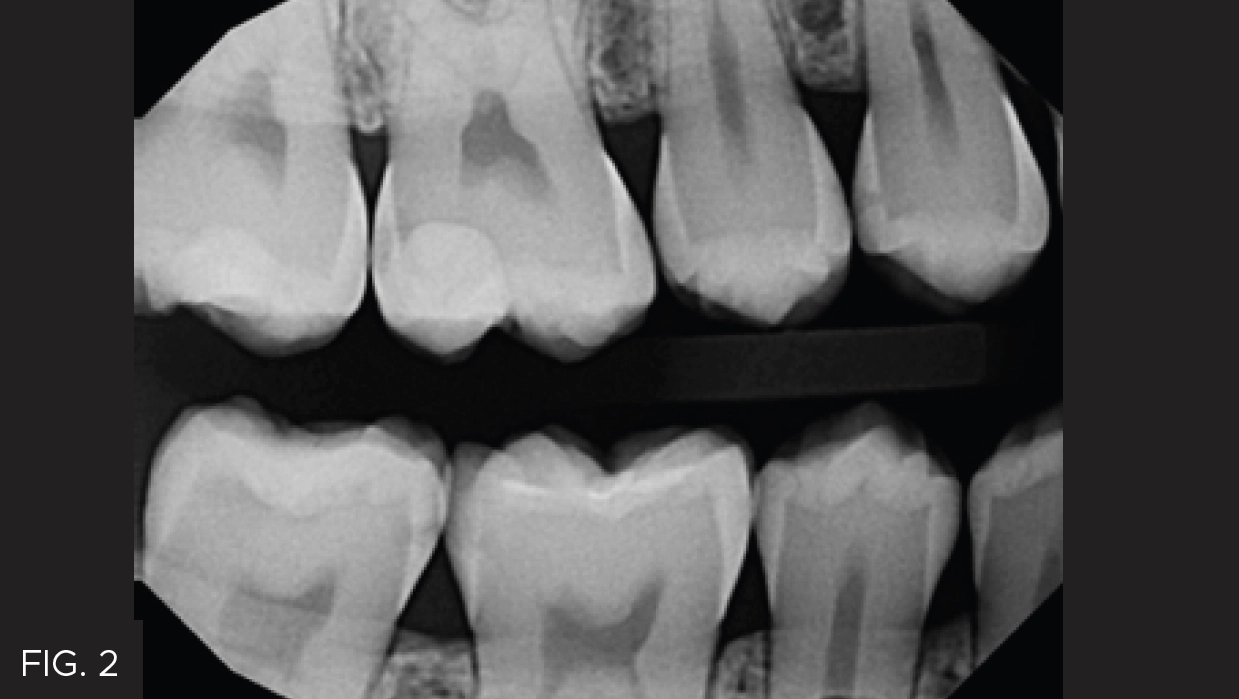

The post-operative result shows a smooth and ideal contour with a tight interproximal contact. (FIG. 6) These characteristics are critical in obtaining a result that yields easy cleansability and less potential for postoperative sensitivity. Utilizing the DualForce Matrix System allows for a predictable and reliable outcome to help achieve clinical success for your patients.